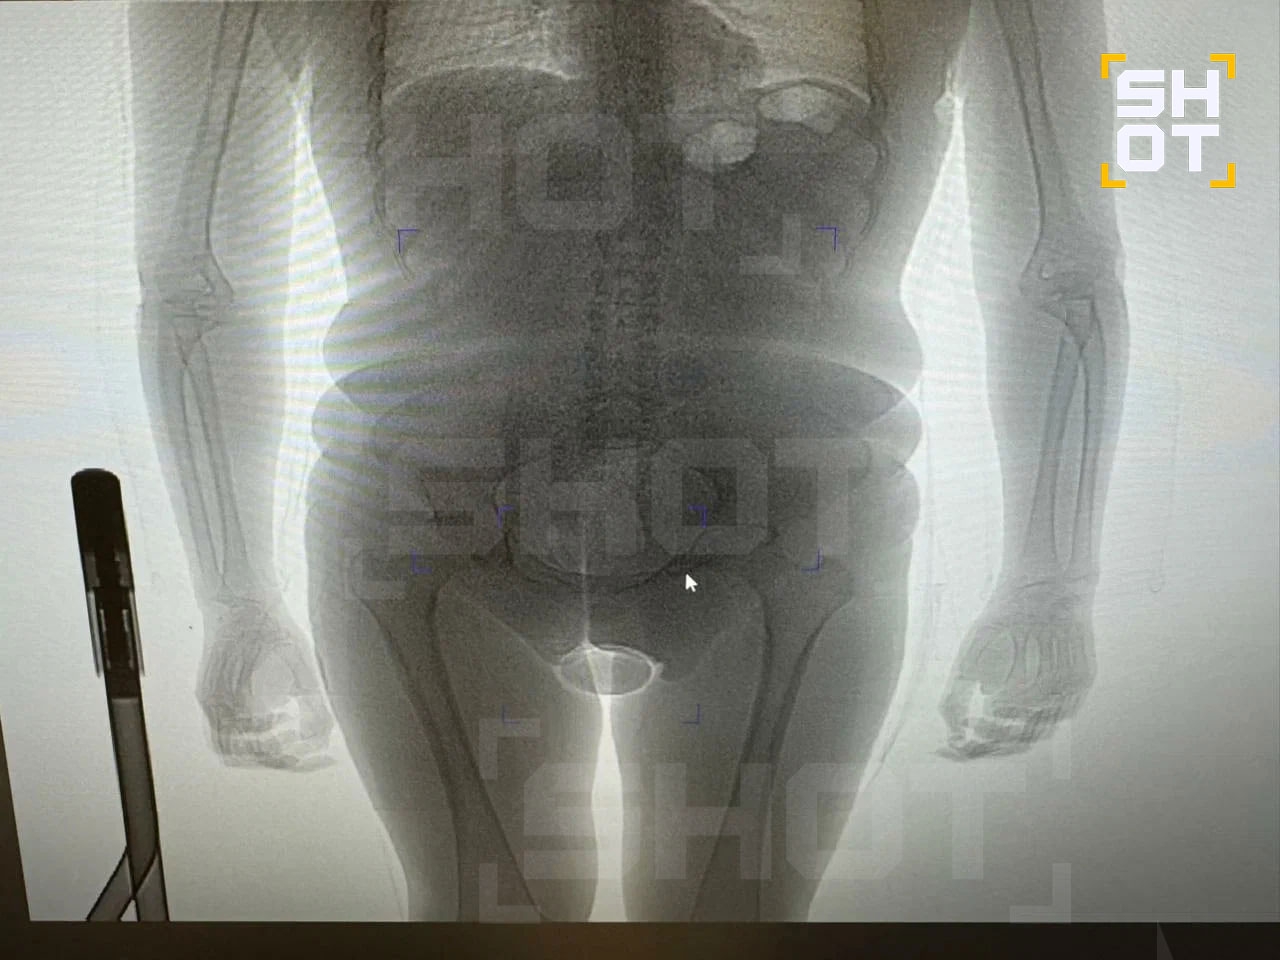

Наркокурьер-транспидор из Бразилии задержана в Домодедово. 22-летнее тело пыталось, провезти кокаин в презервативах, спрятанных в заднице. Подозрительного пассажира, прилетевшегоиз Дубая, остановили таможенники. При просвечивании обнаружились странные предметы внутри его тела. Вытащили презервативы, а там наркота — кокс массой 250 граммов. Оказалось, что дама — бывший мужик.